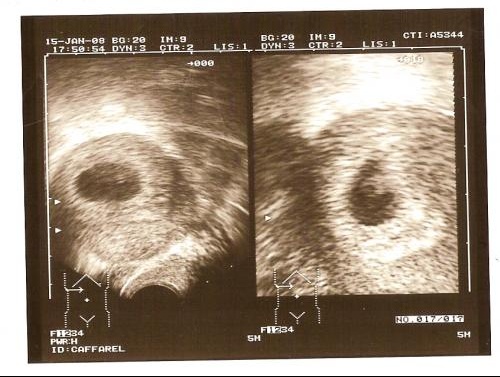

Echo bébé 6 semaines

Echo bébé 6 semaines- Selon la « nub theory » ou méthode du bourgeon génital, on peut, dès 12 semaines d'aménorrhée environ, avoir une idée du sexe de bébé en étudiant l'angle entre le bourgeon et la colonne vertébrale Chez un garçon, le bourgeon forme un angle d'approximativement 30 degrés avec la colonne vertébrale Si cet angle est inférieur à 30 degrés ou si le bourgeon est parallèle • et les femmes enceintes aux 2e et 3e trimestres (13 semaines et plus) Afin de diminuer les risques de transmission, la vaccination est aussi offerte gratuitement aux gens vivant sous le même toit que les personnes nommées précédemment, à leurs aidants naturels, aux personnes qui résident avec un bébé de moins de 6 mois et aux travailleurs de la santé Par

3 Ma 2nde Echo A 6 Semaines De Grossesse 8 Semaines Amenorrhee Bebe Story